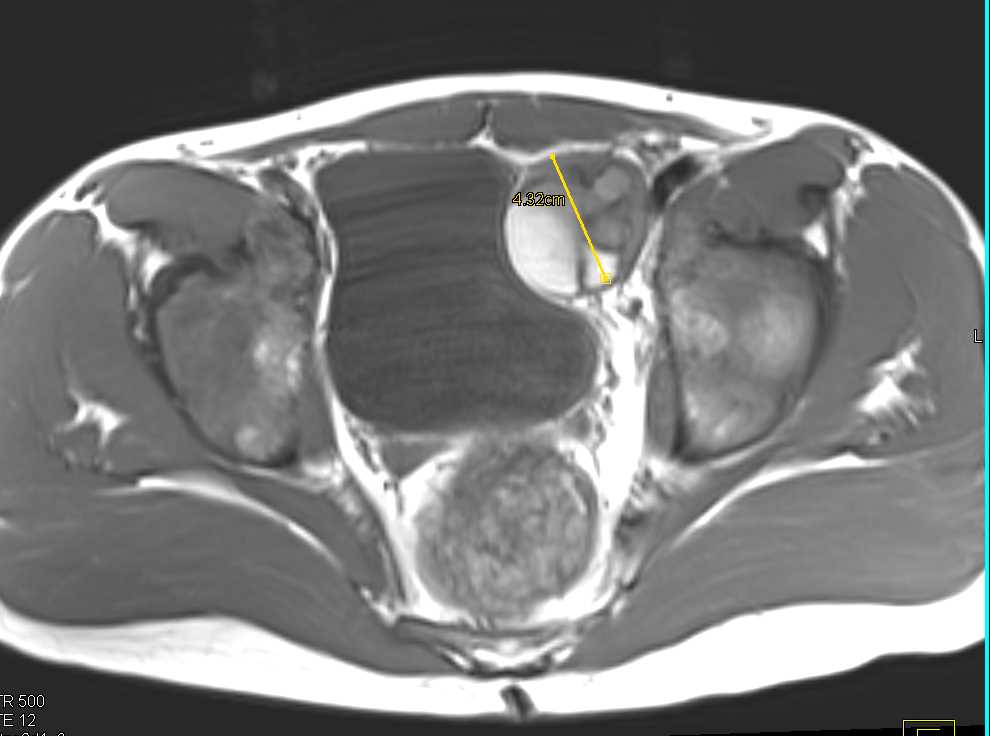

Pelvic Ewing Sarcoma